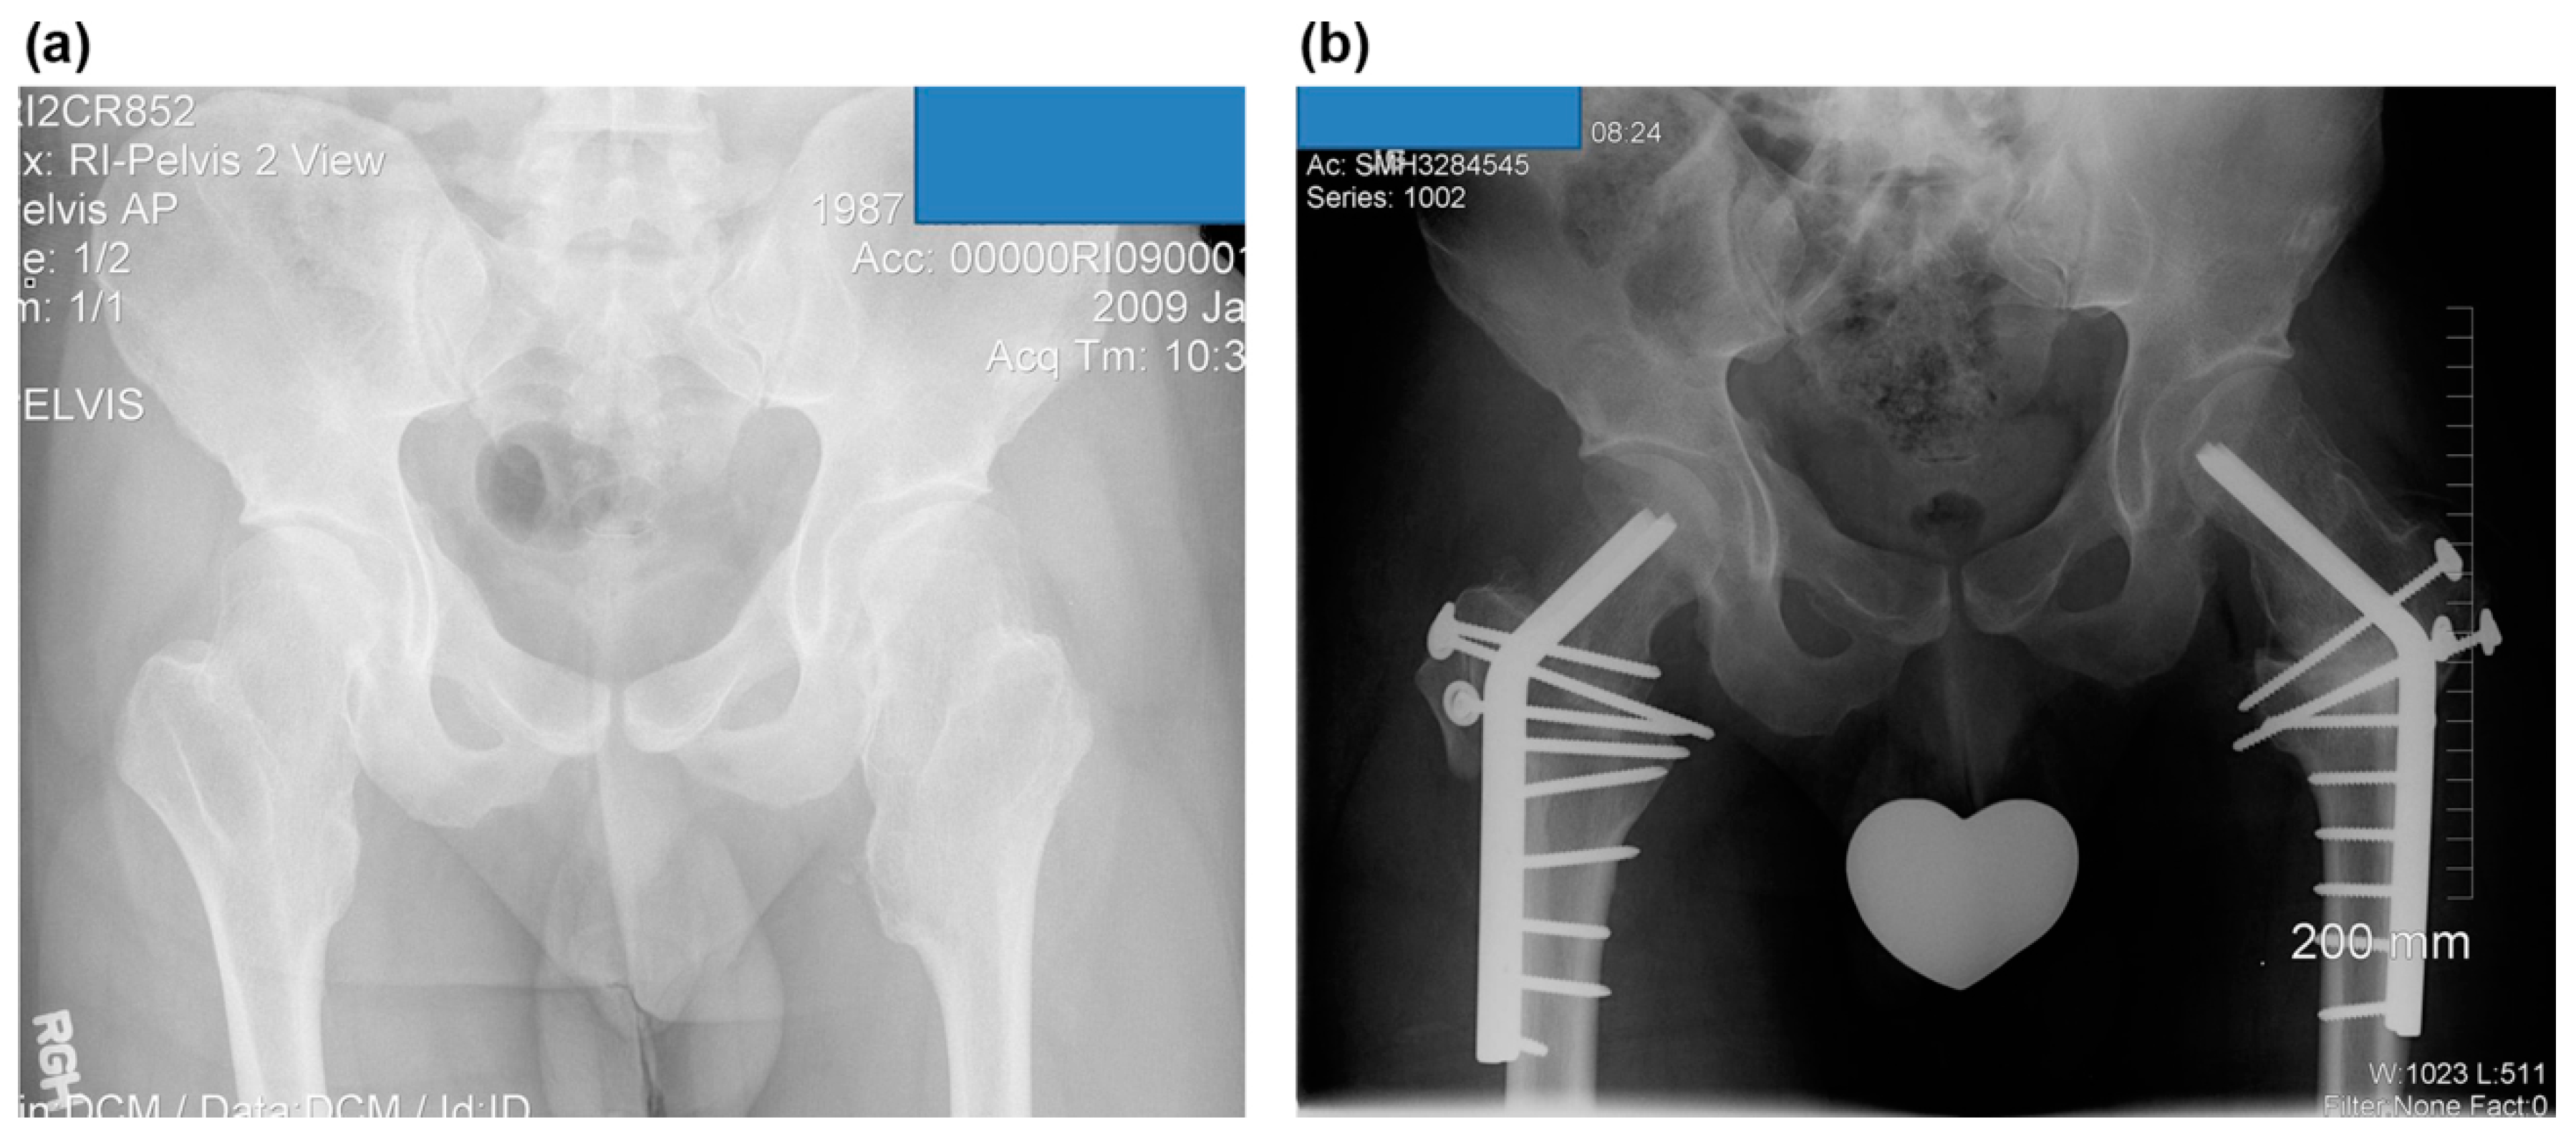

Figure 2.

The images illustrate the case of a 14-year-old boy with Langer–Giedion syndrome (case no. 3). (a) Preoperative anteroposterior radiograph of the left hip shows osteochondromas at the femoral head and a completely dislocated hip. (b) Dislocated hip.

Osteochondromas were noted around the femoral neck in nine cases. The medial side of the femoral neck was involved in all patients, posterior in nine of ten hips, and anterior in eight. Osteochondromas involved the femoral head in the Langer–Giedion syndrome (Figure 1). NSR in mediolateral width was improved with surgery from a mean of 3.3 (range, 2.1–6.7) to 1.8 (range, 1.0–3.0) and in the anteroposterior width from 2.7 (range, 1.9–4.3) to 1.4 (range, 0.8–2.1). Neck–shaft angle was improved from a mean of 157° (range, 135°–180°) to 139° (range, 130°–150°); and center-edge angle from 20° (range, 0°–30°) to 30° (range, 25°–40°). Sharp’s acetabular angle was 44° on average (range, 40°–45°) preoperatively. Shenton’s line was broken in six hips and postoperatively reduced in all cases (Table 3).

Several hip deformities have been documented including femoral anteversion, coxa valga, acetabular dysplasia, and hip subluxation [4,5,9,10,34,35]. Lesion incidence of the proximal femur has been reported as 30–90%, and of the coxa valga as 25% [1,6,7,34,35]. A true developmental hip dysplasia may result from mechanical insufficiency of the acetabular cavity due to osteochondromas of the proximal femur and from coxa valga [10,36]. Consequently, subluxation of the hip occurs due to the effect of the osteochondroma pushing the hip out of the joint combined with the effect of the valgus of the femoral neck [9,10]. Complete dislocation of the hip can even occur, as presented in this series (Figure 1). Furthermore, severe MHE can result in total hip replacement [14]. Additional corrective osteotomy should be considered at index surgery to restore adequate congruency of the hip joint to prevent this deteriorative course. Six hips (60%) were necessary to undergo additional corrective osteotomies in this series.